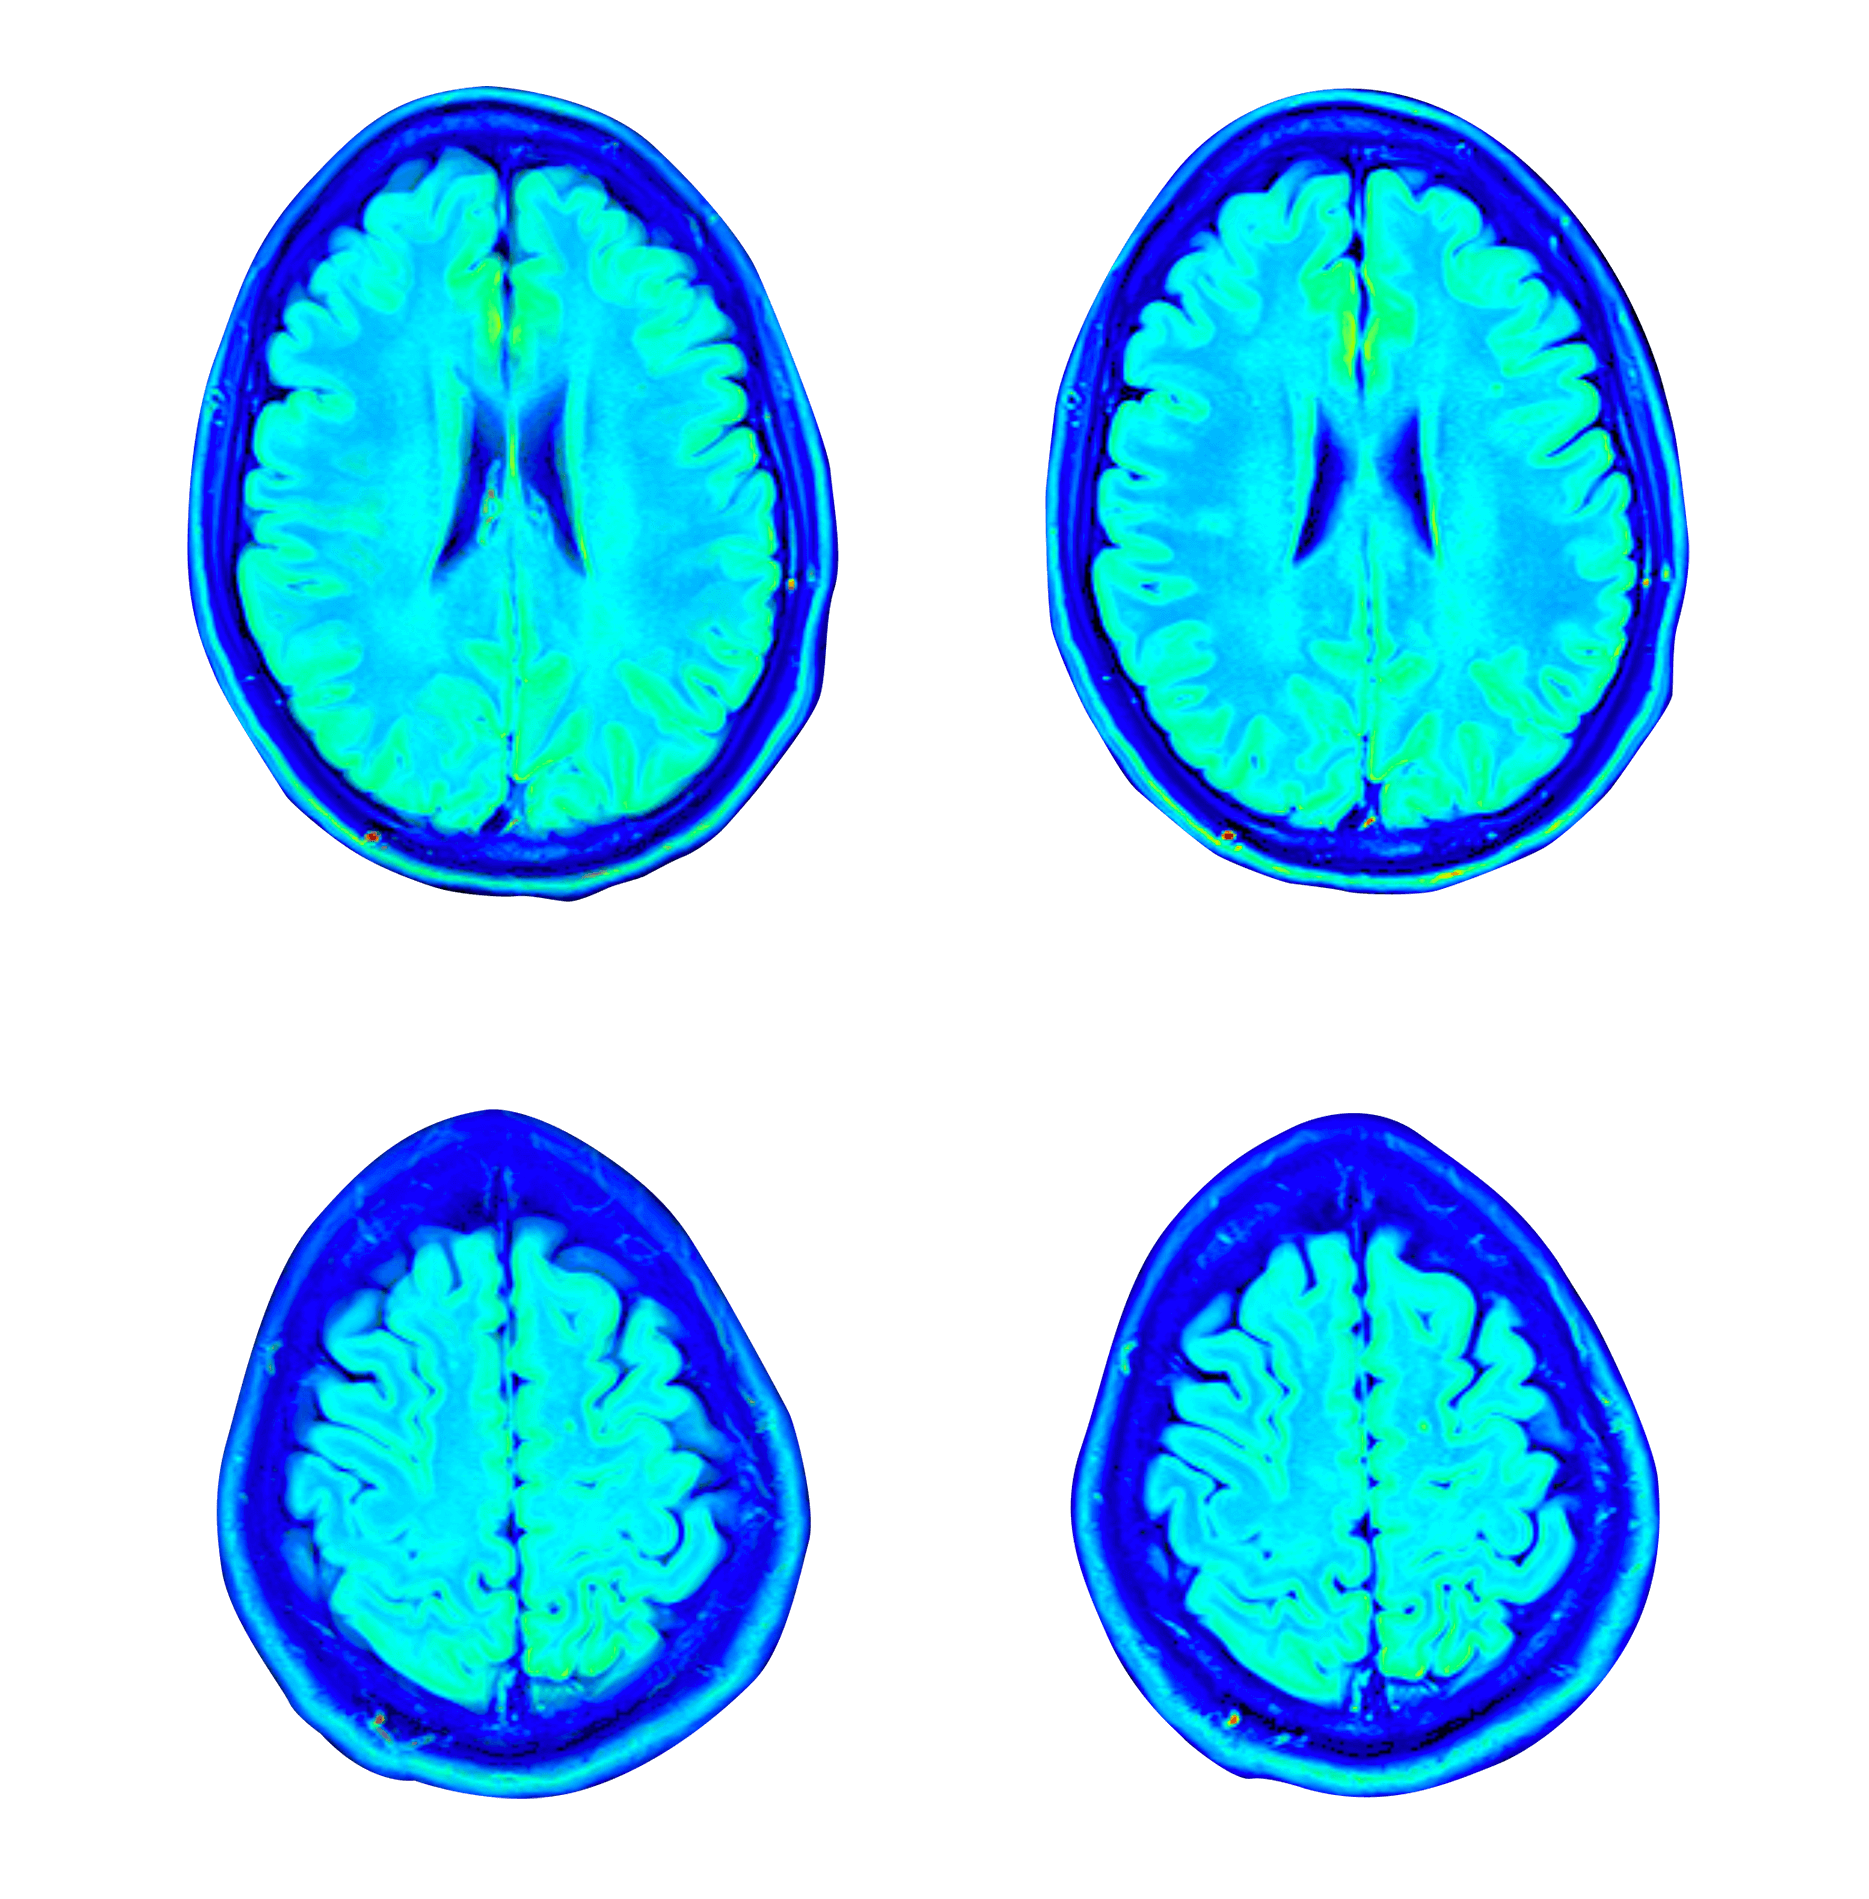

تقييم طبي متكامل

تقييم طبي وفسيولوجي وذهني شامل على مدار ثلاثة أيام، يشمل أكثر اختبارات تصوير الدماغ تطوراً بما يتناسب مع احتياجاتك – مثل التصوير بالرنين المغناطيسي لتروية الدماغ MRI، والتصوير بالرنين المغناطيسي الوظيفي fMRI، والتصوير المقطعي المحوسب بفوتون واحد SPECT – وتقييم مخبري متطور للألم. ويقوم بإجراء هذه الفحوصات من قبل الطاقم الطبي المعتمد في مركز التميّز الذهني والبدني، والذي يضم نخبة من الأطباء، وخبراء علم النفس العصبي، والمعالجين الفيزيائيين، وأخصائي علم وظائف الأعضاء، وفريق التمريض.